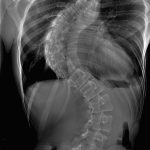

Un adolescent de 16 ani, din județul Botoșani, are nevoie de ajutor pentru a lupta cu o boală grea. Mario, din Bucecea, a fost diagnosticat cu scolioză, o boală întâlnită frecvent, care însă, în cazul lui a luat o amploare de o gravitate ieșită din comun. Coloana vertebrală a baiatului s-a înclinat la 98 de grade, iar acum doar o operație costisitoare la Spitalul Monza din București îl mai poate salva și îi poate reda viața cât de cât normală. Operația costă însă 23.000 de euro, bani pe care familia nu îi are.

„Dacă poartă corset și o bluză, malformația nu se vede așa tare, dar puteți vedea pe radiografie cum este. Dacă nu se intervine din punct de vedere chirurgical, atunci baiatul meu nu va putea să aibă o viață normală de adult. Doctorii sunt optimiști și spun că operația va avea succes, însă costurile sunt enorme pentru noi”, spune tatăl băiatului.